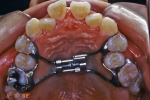

製作したナンス

製作したナンス 口腔内にセット

口腔内にセット

構造

パラータルバーと似たような構造ですが、500円玉大の円盤状のパットが、つかえ棒のように張り付いて、奥歯が前にズレて来ないよう押さえるような構造になっています。パラータルバーと同じで、左の図のように、石膏模型上で製作します。